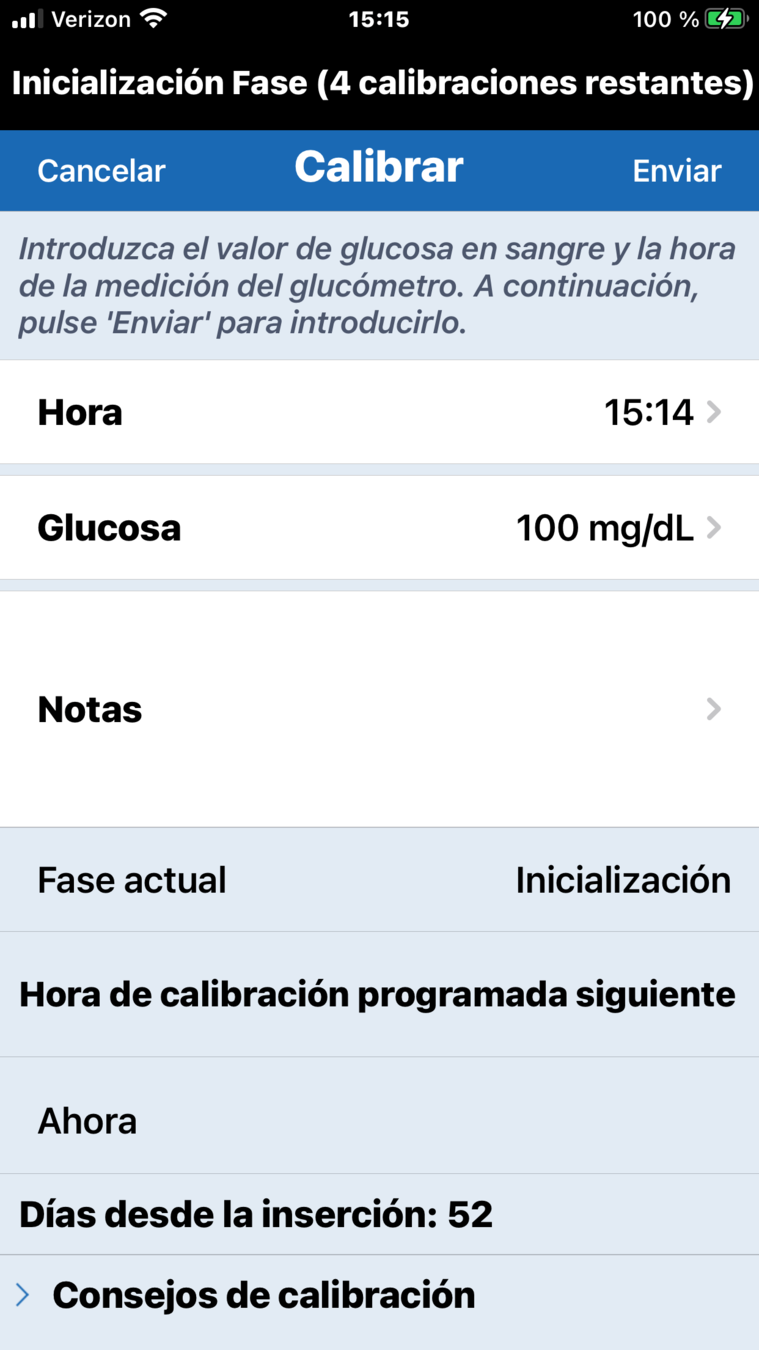

Para introducir una calibración, haga una comprobación de glucosa en sangre mediante punción capilar…

… y toque en el botón Calibrar.

Toque Glucosa…

… y desplácese para introducir el valor correcto de glucosa en sangre.

A continuación, toque OK.

Confirme que se han introducido los valores correctos de glucosa y, a continuación, toque Enviar.

Recibirá una notificación de Calibración en curso, que podrá borrar pulsando Terminado.